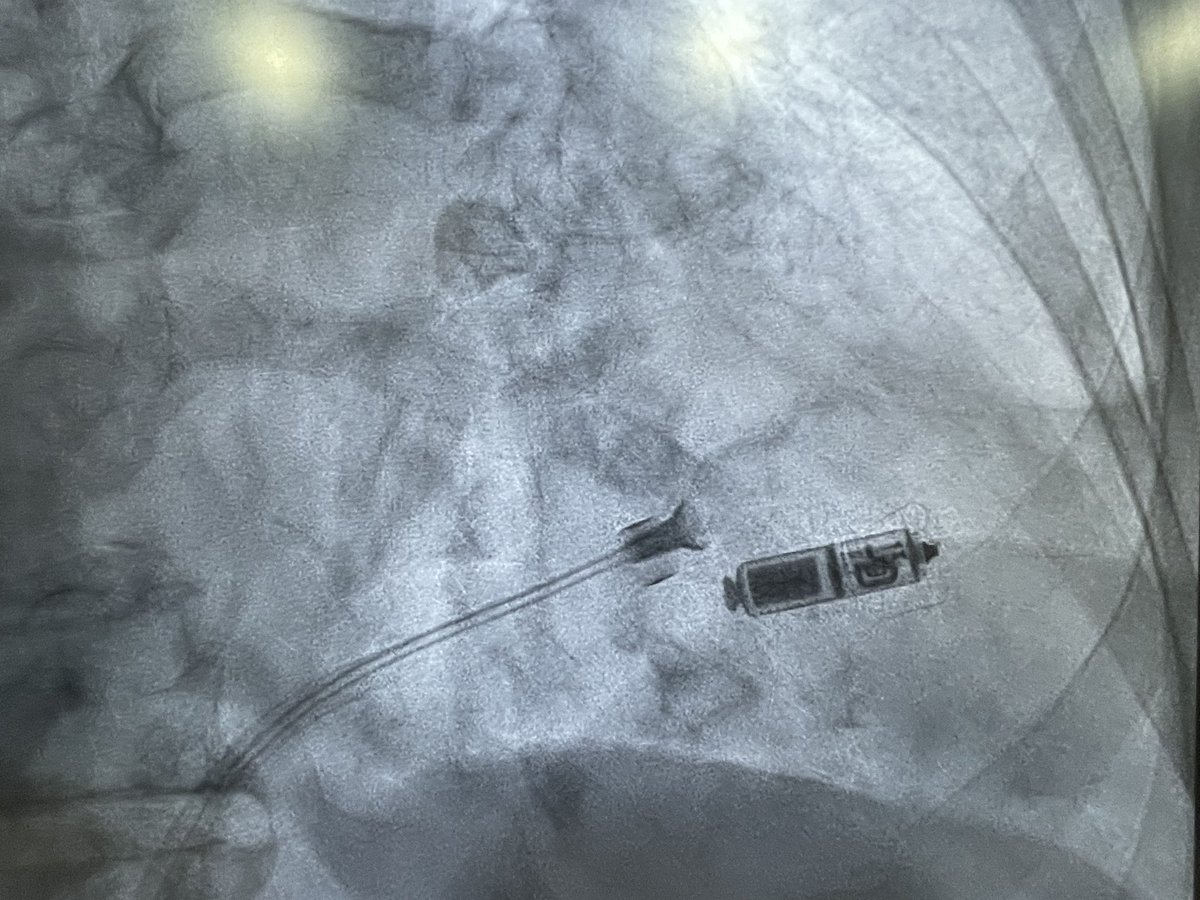

Dual chamber Leadless AVEIR pacemaker at Apollo Chennai - first in Tamilnadu and Apollo Group. - innovative, revolutionary, minimally invasive solution that ensures faster recovery and lasting comfort with physiological pacing. @Pacemaker @Apollo_Chennai @AbbottNews